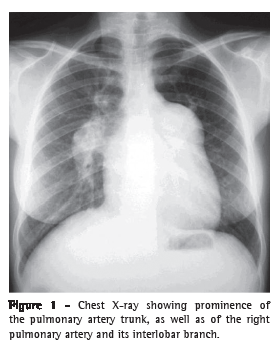

An ultrasound scan of the abdomen revealed moderate central and peripheral echogenic periportal thickening, gallbladder wall thickening, with signs of portal hypertension (portal vein = 13 mm and splenic vein = 10 mm), and an 11-mm paraumbilical vein as a pathway of collateral circulation, all of which are consistent with hepatosplenic schistosomiasis. The longitudinal diameter of the spleen was 117 mm. At the first assessment, upper digestive tract endoscopy revealed small-diameter esophageal varices. The serology was negative for hepatitis B surface antigen (HBsAg), antibody to hepatitis B surface antigen (anti-HBs), antibody to hepatitis B core antigen (anti-HBc), and antibody to hepatitis C virus (anti-HCV). A chest X-ray showed dilated pulmonary arteries and right heart enlargement (Figure 1), both of which were confirmed by chest CT (Figure 2). An electrocardiogram showed signs of right heart overload. An echocardiogram revealed right atrial and right ventricular enlargement, with an estimated pulmonary artery systolic pressure of 145 mmHg, as well as aneurysmal dilatation of the pulmonary artery (56 mm). The spirometry results were as follows: FEV1 = 2.22 L (76%); FVC = 3.04 L (90%); FEV1/FVC = 73.03%; and a negative bronchodilator test. The 6MWD was 153.6 m, and the test was interrupted, due to presyncope, at 75 s. Angiotomography and lung scintigraphy, which had been performed previously, revealed aneurysmal dilatation of the pulmonary artery, no pulmonary artery filling defects, and a low probability of pulmonary embolism. Right heart catheterization showed a pulmonary artery systolic pressure of 140 mmHg, a mean pulmonary artery pressure of 88 mmHg, a cardiac index of 3.0 L min−1 m−2, and pulmonary vascular resistance of 23.0 Woods. Pulmonary vasoreactivity testing with nitric oxide was negative.

Data from facilities specializing in the treatment of patients with PH in Brazil suggest that schistosomiasis is the cause of the disease in at least 30% of such patients.(16) The clinical presentation seems to be similar to that of idiopathic PAH, being characterized by dyspnea on exertion, weakness, cough, palpitation, chest pain, and hemoptysis.(16) Chest X-ray usually shows dilatation of the pulmonary artery trunk and cardiomegaly due to right ventricular enlargement.(17,18)